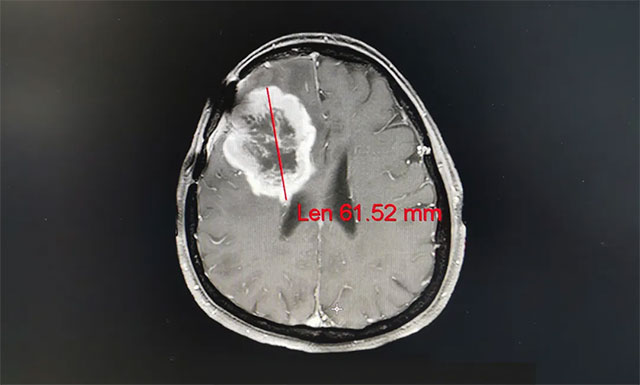

▲ 患者腦膠質(zhì)瘤復(fù)發(fā),癥狀嚴重不能自理

完善其各項檢查,王曉東主任根據(jù)姚女士的臨床資料、病理診斷和影像結(jié)果,確定患者滿足放療條件,并制定了完善周密的放療計劃。之后患者進行了一個療程(30次)的放射治療,放療期間未見明顯不良反應(yīng),經(jīng)過放射治療,姚女士的病灶由原來的61.52mm縮小到50.33mm;其頭痛、惡心癥狀明顯改善,大小便也恢復(fù)正常,走路不穩(wěn)的癥狀也得到了緩解。

▲ 經(jīng)過放射治療患者病灶變小,其癥狀明顯改善